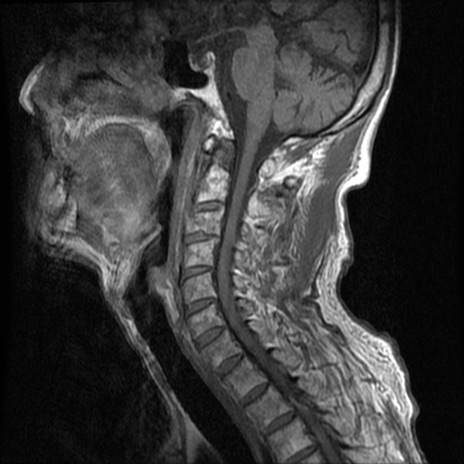

頚椎MRI

T1WI(横断像)

T2*WI(横断像)

T2WI(矢状断像)